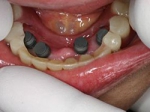

片側2歯欠損片側2歯欠損片側2歯欠損 主訴-入れ歯を使ってみたが違和感強くてダメ。固定のものにしたい。術前下顎口腔内(鏡像) 二次オペ時(鏡像)二次オペ時(鏡像)二次オペ時(鏡像) 術後術後術後、左下奥2本インプラント(鏡像) 術後(レントゲン)術後(レントゲン)術後(レントゲン)、左下奥2本インプラント